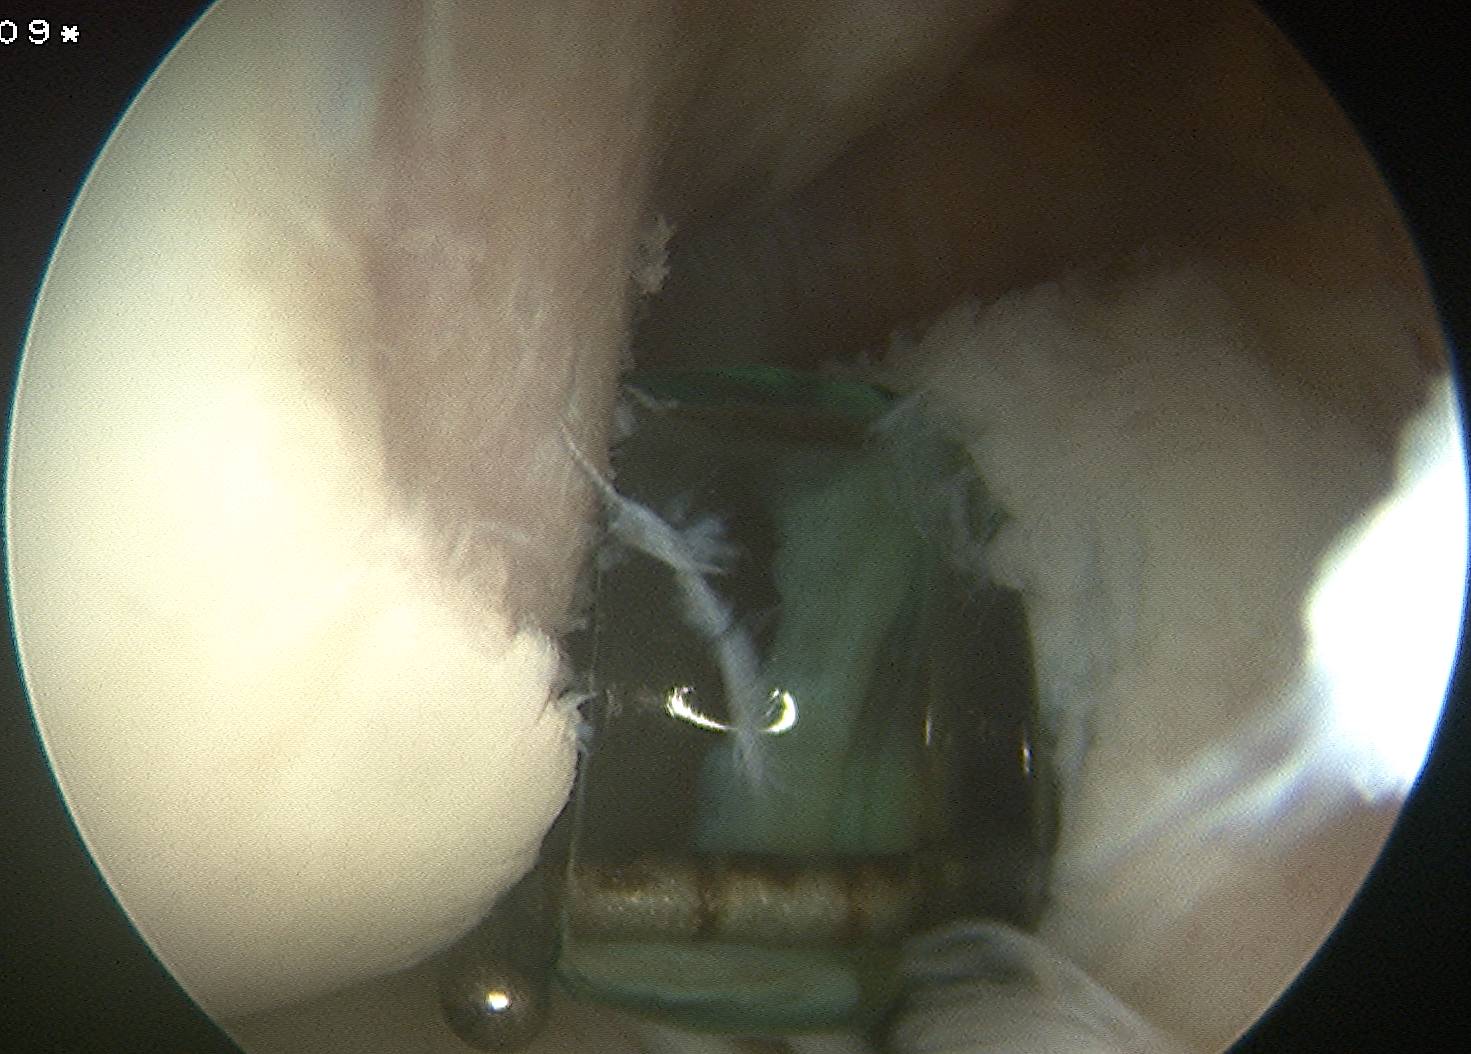

Cruciate ligament ganglion

Technique

Surgical technique PDF using trans-septal portal

- 85 intra-articular ganglions

- 49 ACL, 16 PCL

- 12 from anterior horn meniscus, 3 posterior horn meniscus

- 3 from fat pad

Technique

Surgical technique PDF using trans-septal portal